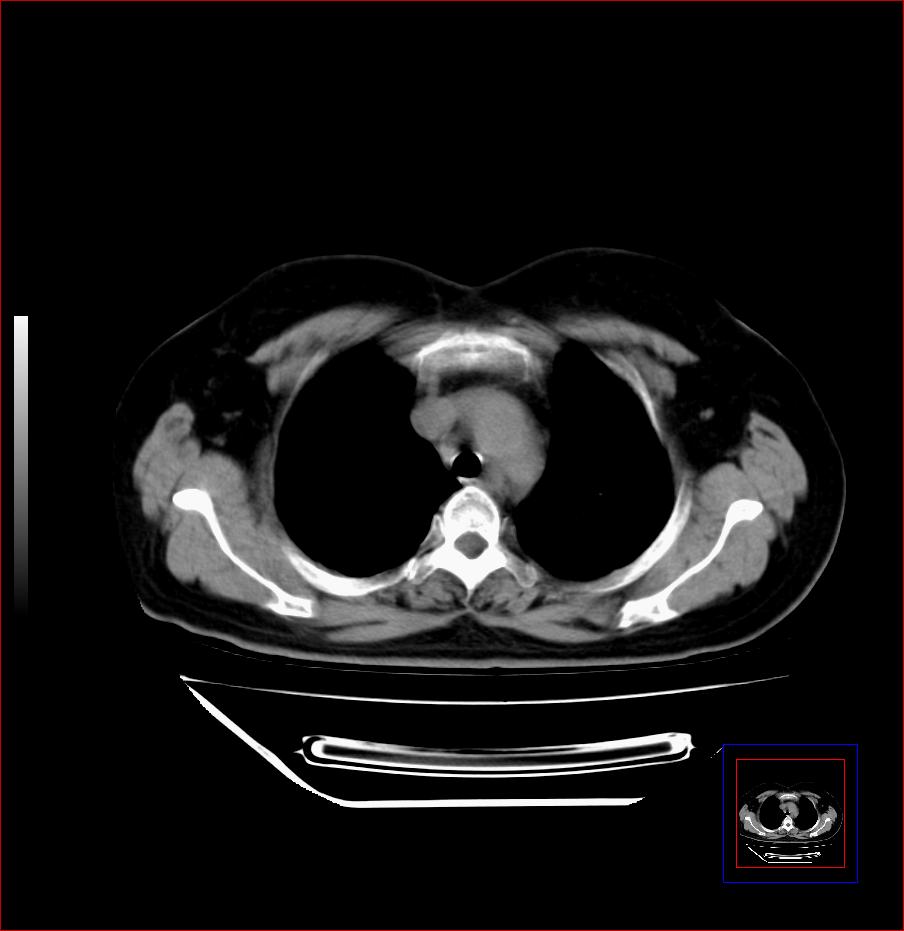

标题: CT25445:上段食管正常吗?

女,56岁,胸部体检,无不适。感觉食管壁略厚,最后约6mm.谢谢大家讨论,主要是自己亲人,疑神疑鬼的。主动脉弓旁淋巴结还有点肿大。